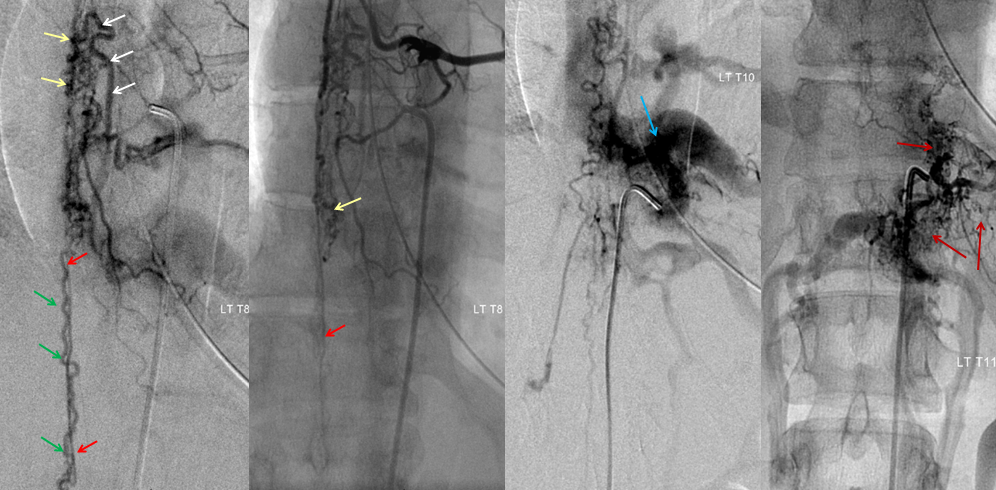

Хирургические процессы при эмболизации гемангиомы на фото

Раздел: Снимки-откровения